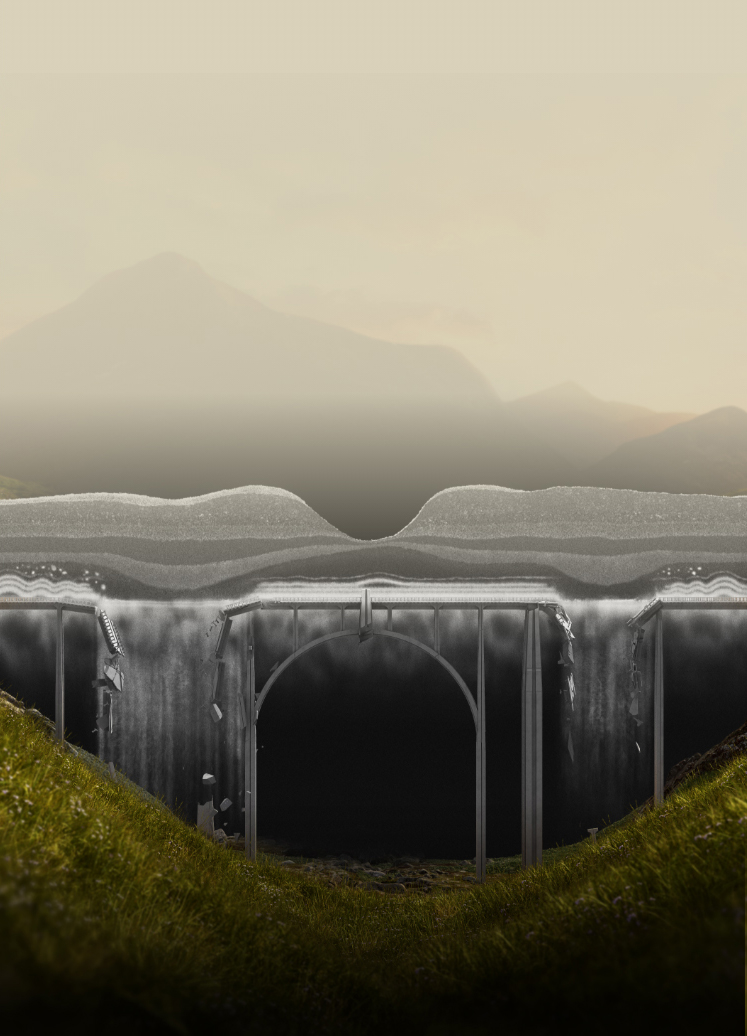

SEE THE SIGNS OF GEOGRAPHIC ATROPHY (GA)

GA can destroy so much

It is critical to recognize GA and refer patients in a timely manner, as disease progression is relentless and irreversible1,4-8